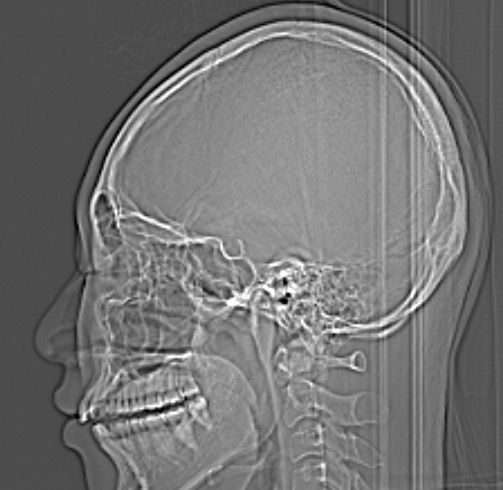

• 2번 째 사진

1. 엑스레이상 큰 문제는 발견되지 않습니다.

2. 단지 소리만 나는 것은 턱관절 질환으로 분류하지 않습니다. 소리가 나는 증상 외에 턱관절 통증, 입 안벌어짐 등의 증상이 동반된다면 구강내과 치과를 가보시기 바랍니다.

3. 모래 갈리는 소리가 난다면 턱관절염의 가능성이 있긴 합니다.